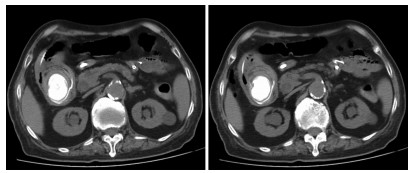

Clinical effect of simultaneous surgical resection of hepatic and pancreatic lesions versus systemic chemotherapy in treatment of resectable pancreatic cancer with liver metastasis

2022, 38(3): 622-628. DOI: 10.3969/j.issn.1001-5256.2022.03.023

Abstract(1500) HTML (1256) PDF (2734KB)(76)

Abstract:

Objective  To investigate the clinical effect of simultaneous surgical resection of hepatic and pancreatic lesions versus systemic chemotherapy in treatment of resectable pancreatic cancer with liver metastasis (PCLM).  Methods  A retrospective analysis was performed for related data of the patients with PCLM who were admitted to Shengjing Hospital of China Medical University from January 2013 to May 2020, and the patients with resectable PCLM were screened out and then divided into surgery group and chemotherapy group. The propensity score matching (PSM) method was used to reduce the impact of data bias and confounding factors. The independent samples t-test or the Mann- Whitney U test was used for comparison of continuous data between two groups, and the chi-square test was used for comparison of categorical data between two groups. The Kaplan-Meier method was used to calculate survival time, and the log-rank test was used for evaluation. The univariate and multivariate Cox regression models were used to investigate the independent risk factors for survival.  Results  A total of 56 patients with resectable PCLM were screened out, with 33 patients in the surgery group and 23 patients in the chemotherapy group, and there were 15 patients in each group after PSM. The surgery group had a significantly shorter median overall survival time than the chemotherapy group before PSM (6.6 months vs 10.4 months, χ2=4.476, P=0.034) and after PSM (6.4 months vs 10.5 months, χ2=4.309, P=0.038). The multivariate Cox regression analysis showed that poorly differentiated tumor (hazard ratio [HR]=4.945, 95% confidence interval [CI]: 1.980-12.348, P=0.001) and absence of postoperative chemotherapy (HR=3.670, 95%CI: 1.437-9.376, P=0.007) were independent risk factors for poor prognosis in patients with PCLM.  Conclusion  Compared with chemotherapy, simultaneous surgical resection of hepatic and pancreatic lesions fails to prolong the overall survival time of patients with resectable PCLM. Patients with poorly differentiated tumor and those without postoperative chemotherapy tend to have poor prognosis.